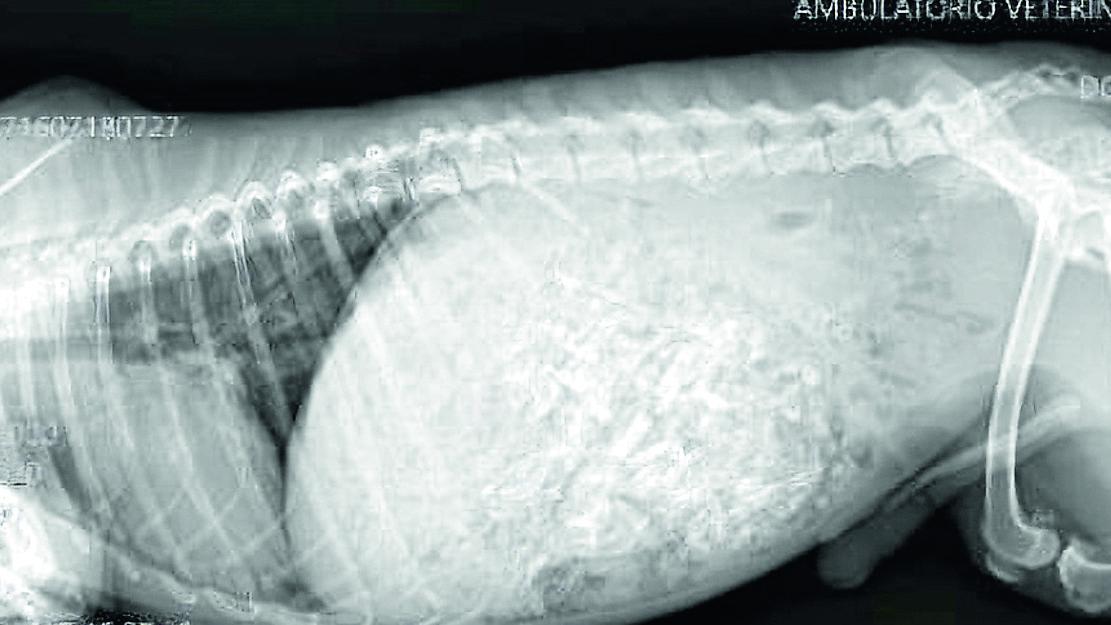

Bosco Mesola Hanno perso il loro cane, Max, e dopo una segnalazione sono andate in una zona di campagna a recuperarlo. Qui in realtà hanno trovato un altro cagnolino, molto simile d’aspetto al loro animale, in pessime condizioni. La sua pancia era enorme: «stava per esplodere perché aveva mangiato una gallina intera». Grazie alle ragazze della toelettatura Pakilù di Bosco Mesola, “Cookie” (così è stato chiamato il cagnolino) è salvo, ma le spese per curarlo ingenti, tanto che è stata aperte una raccolta fondi.

«Le ragazze dopo una segnalazione si sono imbattute nel salvataggio di un cane molto simile - racconta Melania Piva, una delle volontarie più attive nel territorio di Mesola -. Non si sono voltate dall’altra parte e non ci hanno pensato due volte a salvargli la vita. Solo che la cifra dell'intervento è di 970 euro e è stata dunque aperta una raccolta fondi per Cookie». Il cane «era ovviamente denutrito e senza chip, libero in mezzo al nulla con una gallina intera nell’addome. Se volete contribuire alla raccolta per pagare il suo intervento potete passare in toelettatura a Bosco Mesola dalle ragazze». Nel cartello dell’appello, la foto della radiografia e anche del conto della veterinaria che ha comunque chiesto il minimo indispensabile per un intervento del genere. Cookies è stato molto fortunato, mentre non si hanno ancora tracce di Max, perso a Porto Viro: «Offriamo ricompensa senza chiedere niente a chiunque ce lo riporta a casa - l’appello delle titolari di Pakilù -. Max è scomparso dalle 9.30 di sabato. Ha sulla testa dei segnetti neri senza pelo e ha il microchip. Chiamare il 347.33868370, anche solo per segnalazioni che possono essere utili».